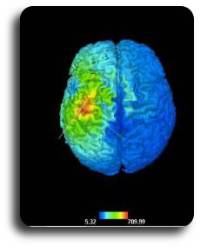

It is possible to store the coil position during the neuronavigation phase, in order to keep this data. Furthermore, it is possible to prearrange the target points manually identified on MRI, or to insert manually target points expressed in Talairach space, which are automatically located on the subject’s MRI. Later on, these points can be reached with the stimulation coil and displayed in 3D in the reconstruction of the scalp or brain. A new function to display target-coil distance enables to optimize the coil position in relation with the subject’s scalp, in order to obtain the maximum effect from the stimulation by reducing as much as possible the distance from the cortex. This function is called “Focus-Distance Map”.

Moreover, the system estimates the potential of the induced electric field on a realistic model of the brain, using the Boundary Element Method (BEM). This mathematical method is based on the spatial position of the coil in relation with the subject, its inclination and the stimulation power used, but also on the coil’s geometry and on its construction features. This estimate is useful in order to evaluate the effects of the magnetic stimulation spread during neuronavigation.